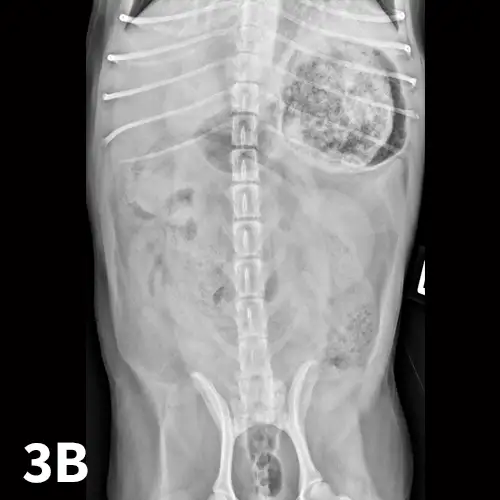

Left lateral (A) and VD (B) survey radiographs of a 4-year-old pit bull terrier with a 3-day history of vomiting, diarrhea, and anorexia. A dilated loop of bowel is present within the midabdomen (star) caudal to the stomach, which could represent large or small bowel.